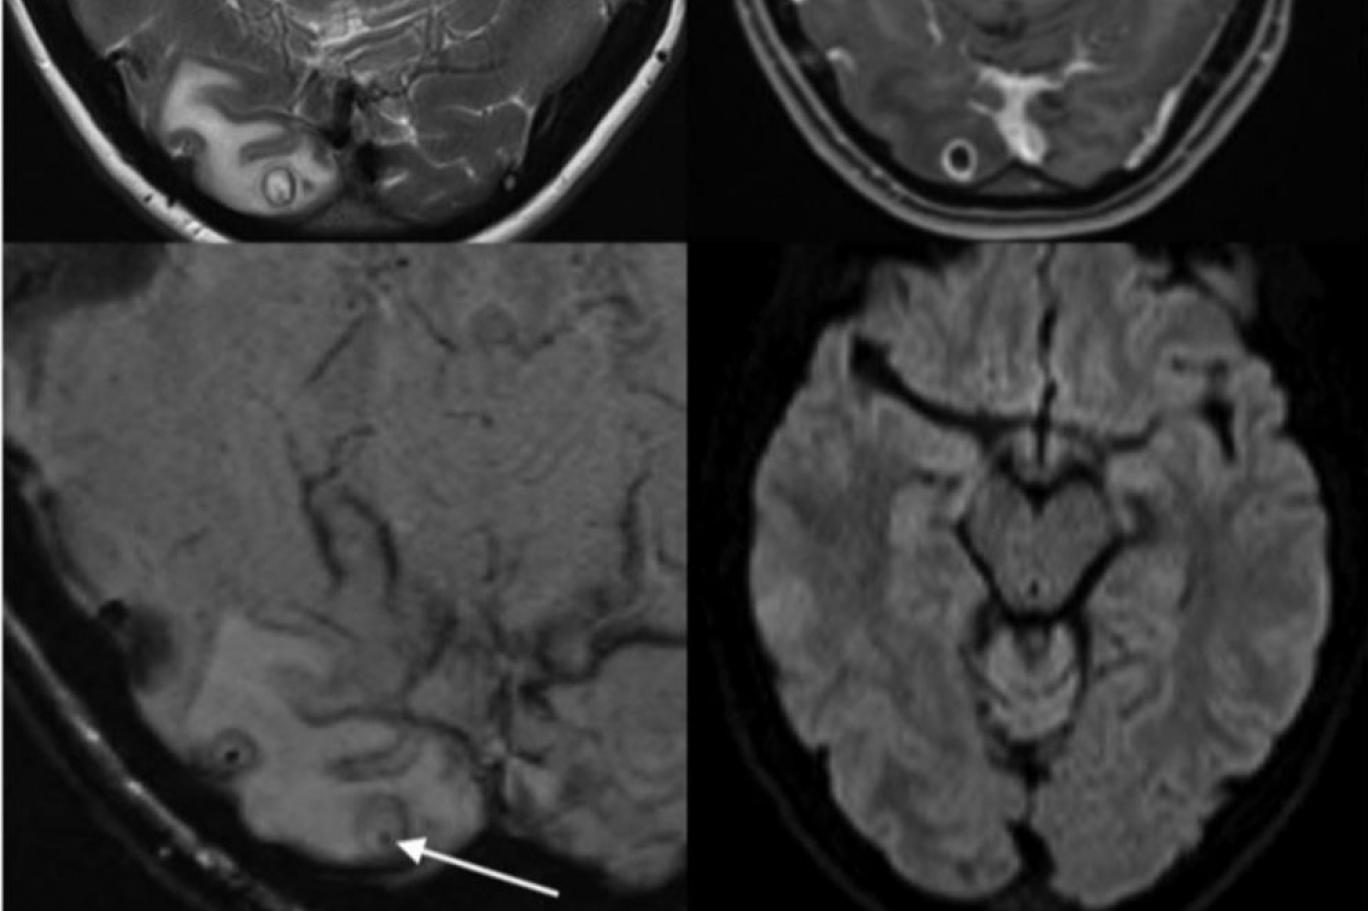

görüşünü dahi etkileyen korkunç baş ağrıları nedeniyle doktorların kapısını çaldı. Adeta kabus gibi günler yaşayan Rostro’nun baş ağrılarının sebeplerini keşfeden doktorlar dehşete düştü… Detaylar diğer sayfada g’örselle devam edin.

Dışkı ile kontamine gıdaların pek çok insanı pas geçtiğini kaydeden Dr. Meyrat, Yadira’nın şanssız olduğunu söyledi.Yadira Rost, şimdi tamamen iyileşmeyi bekliyor. Ama muhtemelen cerrahi görüntüyü hiçbir zaman izlemek istemeyecek…